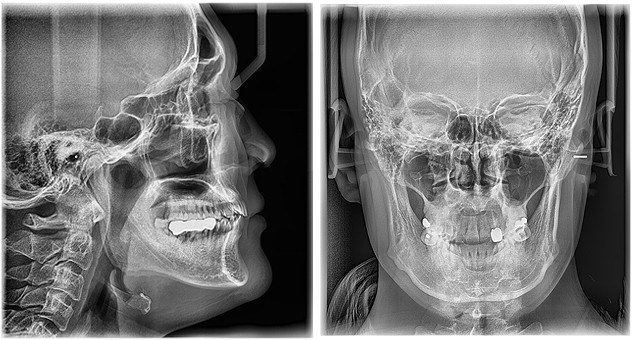

Vatech PaX-i is de meest betaalbare 3 in 1 oplossing, zowel OPG als eventueel 3D en/of Cephalometrische opnames. De Vatech Pax-i is tevens de meest toegankelijke diagnostische röntgenapparatuur ontwikkeld door Vatech. De 'i' staat voor innovatie, één van de kernwaarden van het Koreaanse Vatech. De Vatech Pax-i biedt de meest nauwkeurige en hoogwaardige panoramisch beelden door het innovatieve imaging proces en de opgedane ervaring in de tandheelkunde beeldvorming van Vatech. Het stelt je in staat altijd om een nauwkeurige diagnose te stellen met grote tevredenheid van patiënten in uw praktijk.

- Optimale product keuze voor uw behoefte (OPG, CT, Ceph)